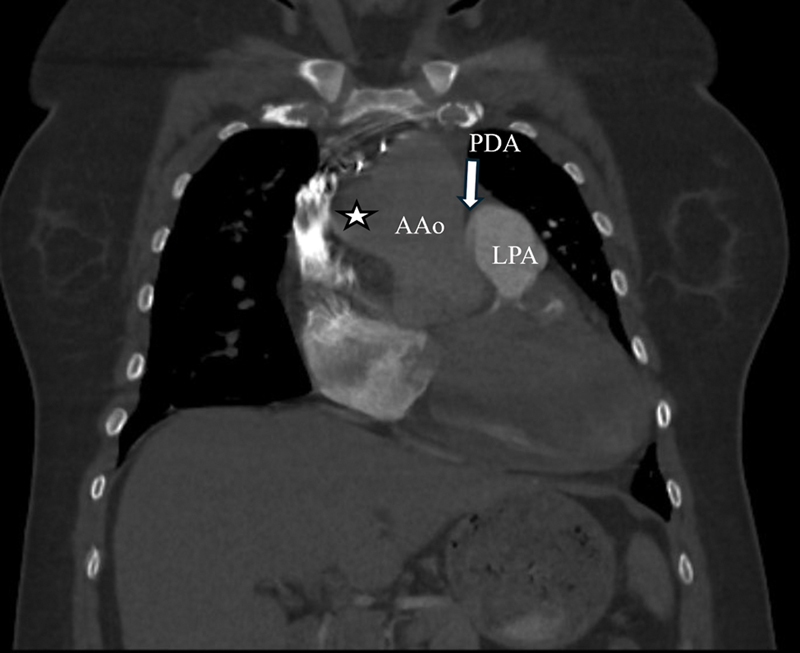

Ectopic origin of the right pulmonary artery (RPA) from the aorta is a rare congenital anomaly typically found in infants. We report an adult female presenting with shortness of breath diagnosed incidentally with ectopic RPA via computed tomography angiography. This case underscores the need to consider rare congenital anomalies in adults presenting with unexplained pulmonary symptoms.